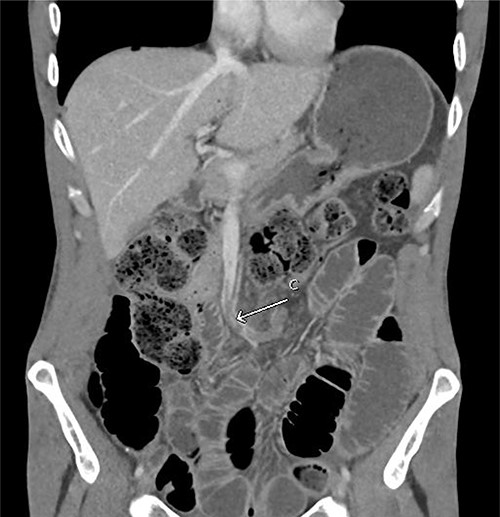

A 43-year-old man presented with acute abdominal pain, nausea and vomiting in the context of not opening his bowels for 10 days. Otherwise, he was a fit and healthy gentleman with no previous abdominal surgeries. He was a light-smoker and did not consume any alcohol or illicit drugs. On presentation, the patient was unwell with diaphoresis and had a rigid abdomen with global peritonism. Rectal examination revealed no blood or mass. Blood tests showed a raised white cell count (27.8/L), borderline elevation of lactate (2.9 mmol/L) and normal C-reactive protein (< 2.0 mg/L). Computed tomography (CT) demonstrated small bowel obstruction with multiple dilated loops with twirling of the mesenteric vessels in central abdomen, as well as moderate ascites (Fig. 1).

Initial CT abdomen pelvis with contrast in the portal venous phase showed (A) dilated small bowel and the (B) classical whirlpool sign.